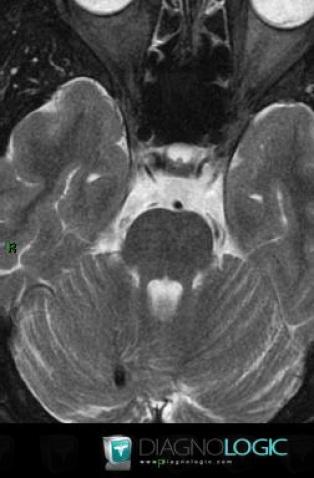

Voici les informations spécifiques à l'image clé ci dessus:

- Diagnostic Anomalie veineuse de développement, Localisation(s) Fosse postérieure, comportant les gammes Lésion infratentorielle en hyposignal T2 ou FLAIR